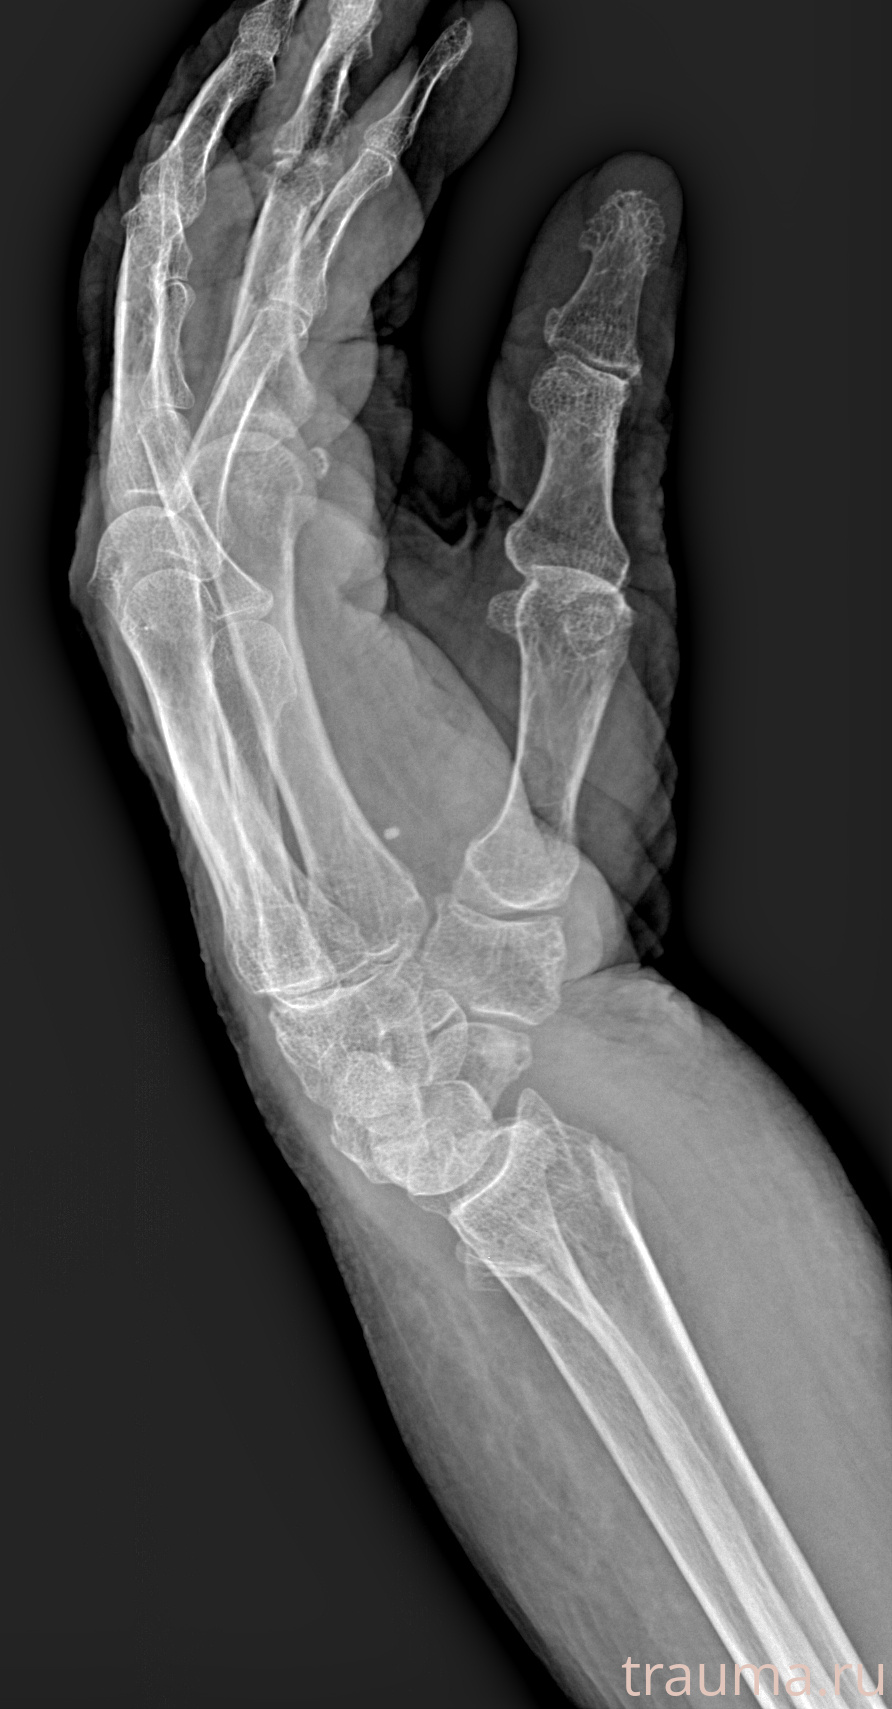

Рентгенограммы

Рентген на дому: по вашему адресу приезжает врач-рентгенолог, травматолог-ортопед с мобильным рентгеновским аппаратом, проводит диагностику травмы или заболевания, делает необходимые рентгенограммы, дает рекомендации по дальнейшему лечению. Получить качественные снимки в домашних условиях возможно благодаря уникальной методике, разработанной МосРентген Центром для института  Склифосовского